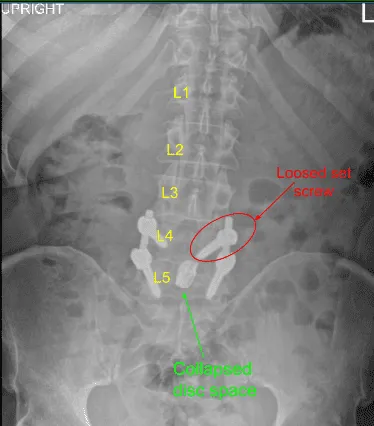

Empezaron a tener síntomas de claudicación. Los observamos y se realizaron nuevas imágenes que mostraron el colapso del espacio interdisco L4-L5 junto con el afloja del tornillo de ajuste de la L4 izquierda.